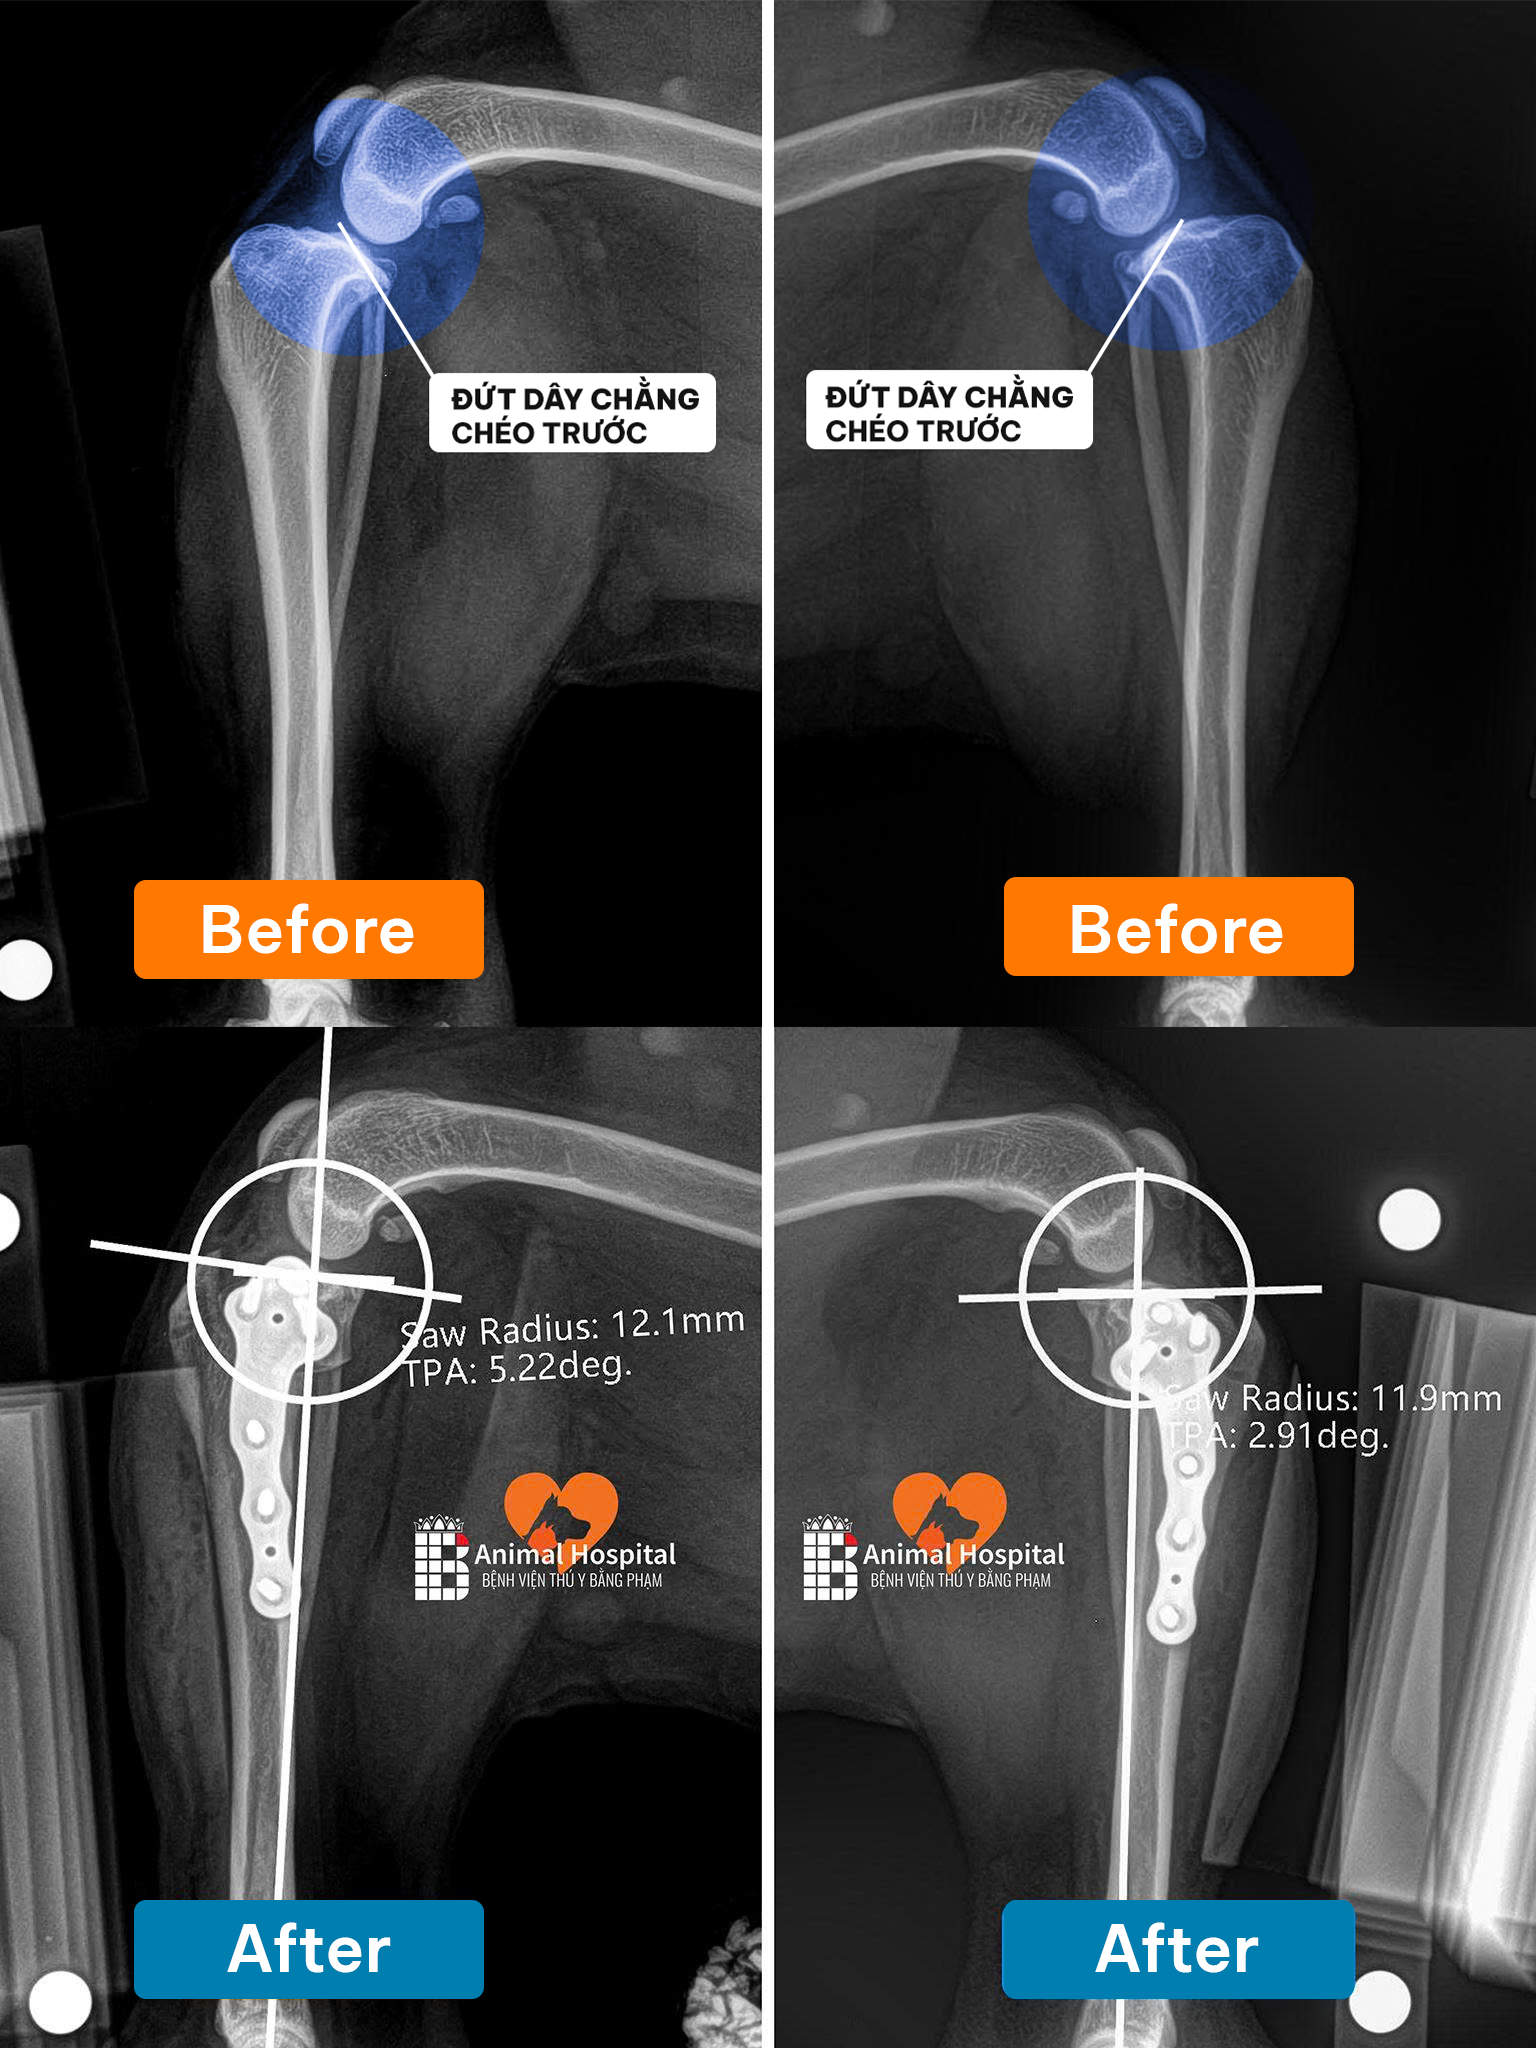

Theo chia sẻ từ gia đình, cách đây 4 năm, Sky từng bị đứt dây chằng khớp háng và đã được điều trị bằng phương pháp cố định nhân tạo.

Chẩn đoán chuyên sâu: Tình trạng thoái hóa ổ cối nghiêm trọng

Qua thăm khám và hình ảnh X-quang, các bác sĩ phát hiện khớp háng của Sky đã bắt đầu tái tổn thương, dẫn đến thoái hóa ổ cối – vị trí tiếp giáp quan trọng giữa chỏm xương đùi và xương chậu.

Kết quả chiếu chụp cho thấy những hư hại nặng nề:

- Ổ cối đã bị xơ hóa nghiêm trọng.

- Cấu trúc khớp bị biến dạng.

- Mất kết nối hoàn toàn giữa chỏm xương đùi và xương chậu.

Chính điều này khiến khớp háng mất đi sự ổn định, gây đau đớn kéo dài và làm suy giảm nghiêm trọng khả năng vận động của Sky.